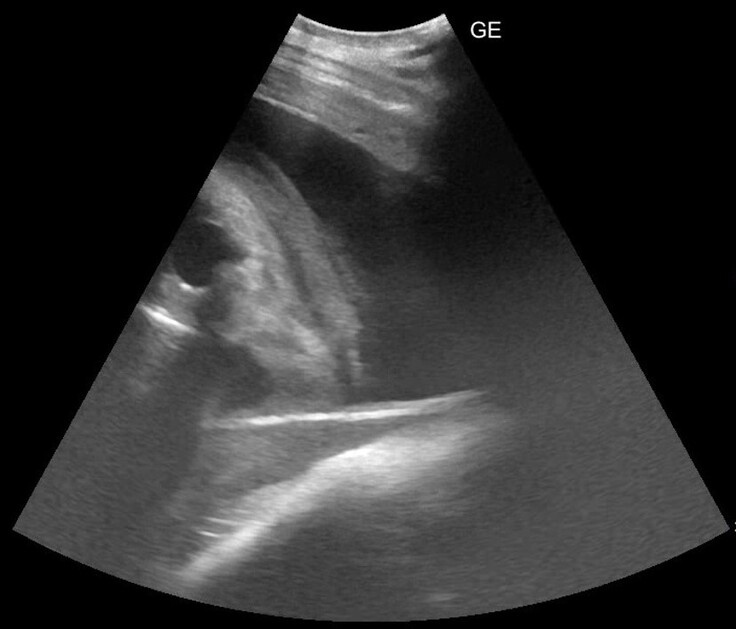

今回の検査で見ることができた画像を紹介します。

これだと何が映っているのかよくわからないので、線を引いてみました。

最初の画像と見比べていただくと、何となく見えてくるでしょうか。メイのお腹の中の子ゾウの前肢と頭です。目に見える黒い部分が、目なのか、鼻の奥を捉えることができたのかははっきりせず、今後の検査で姿勢があえば追っていく予定です。

クラウドファンディングページで紹介した2024年9月の画像では、胸からお腹にかけてを1つの視野で観察できていました。約半年がたち、検査機器で見ることができる25㎝程度の深さでは、たまたま近くに来ている頭の一部や前あしの一部が観察できる、というところまで成長しています。